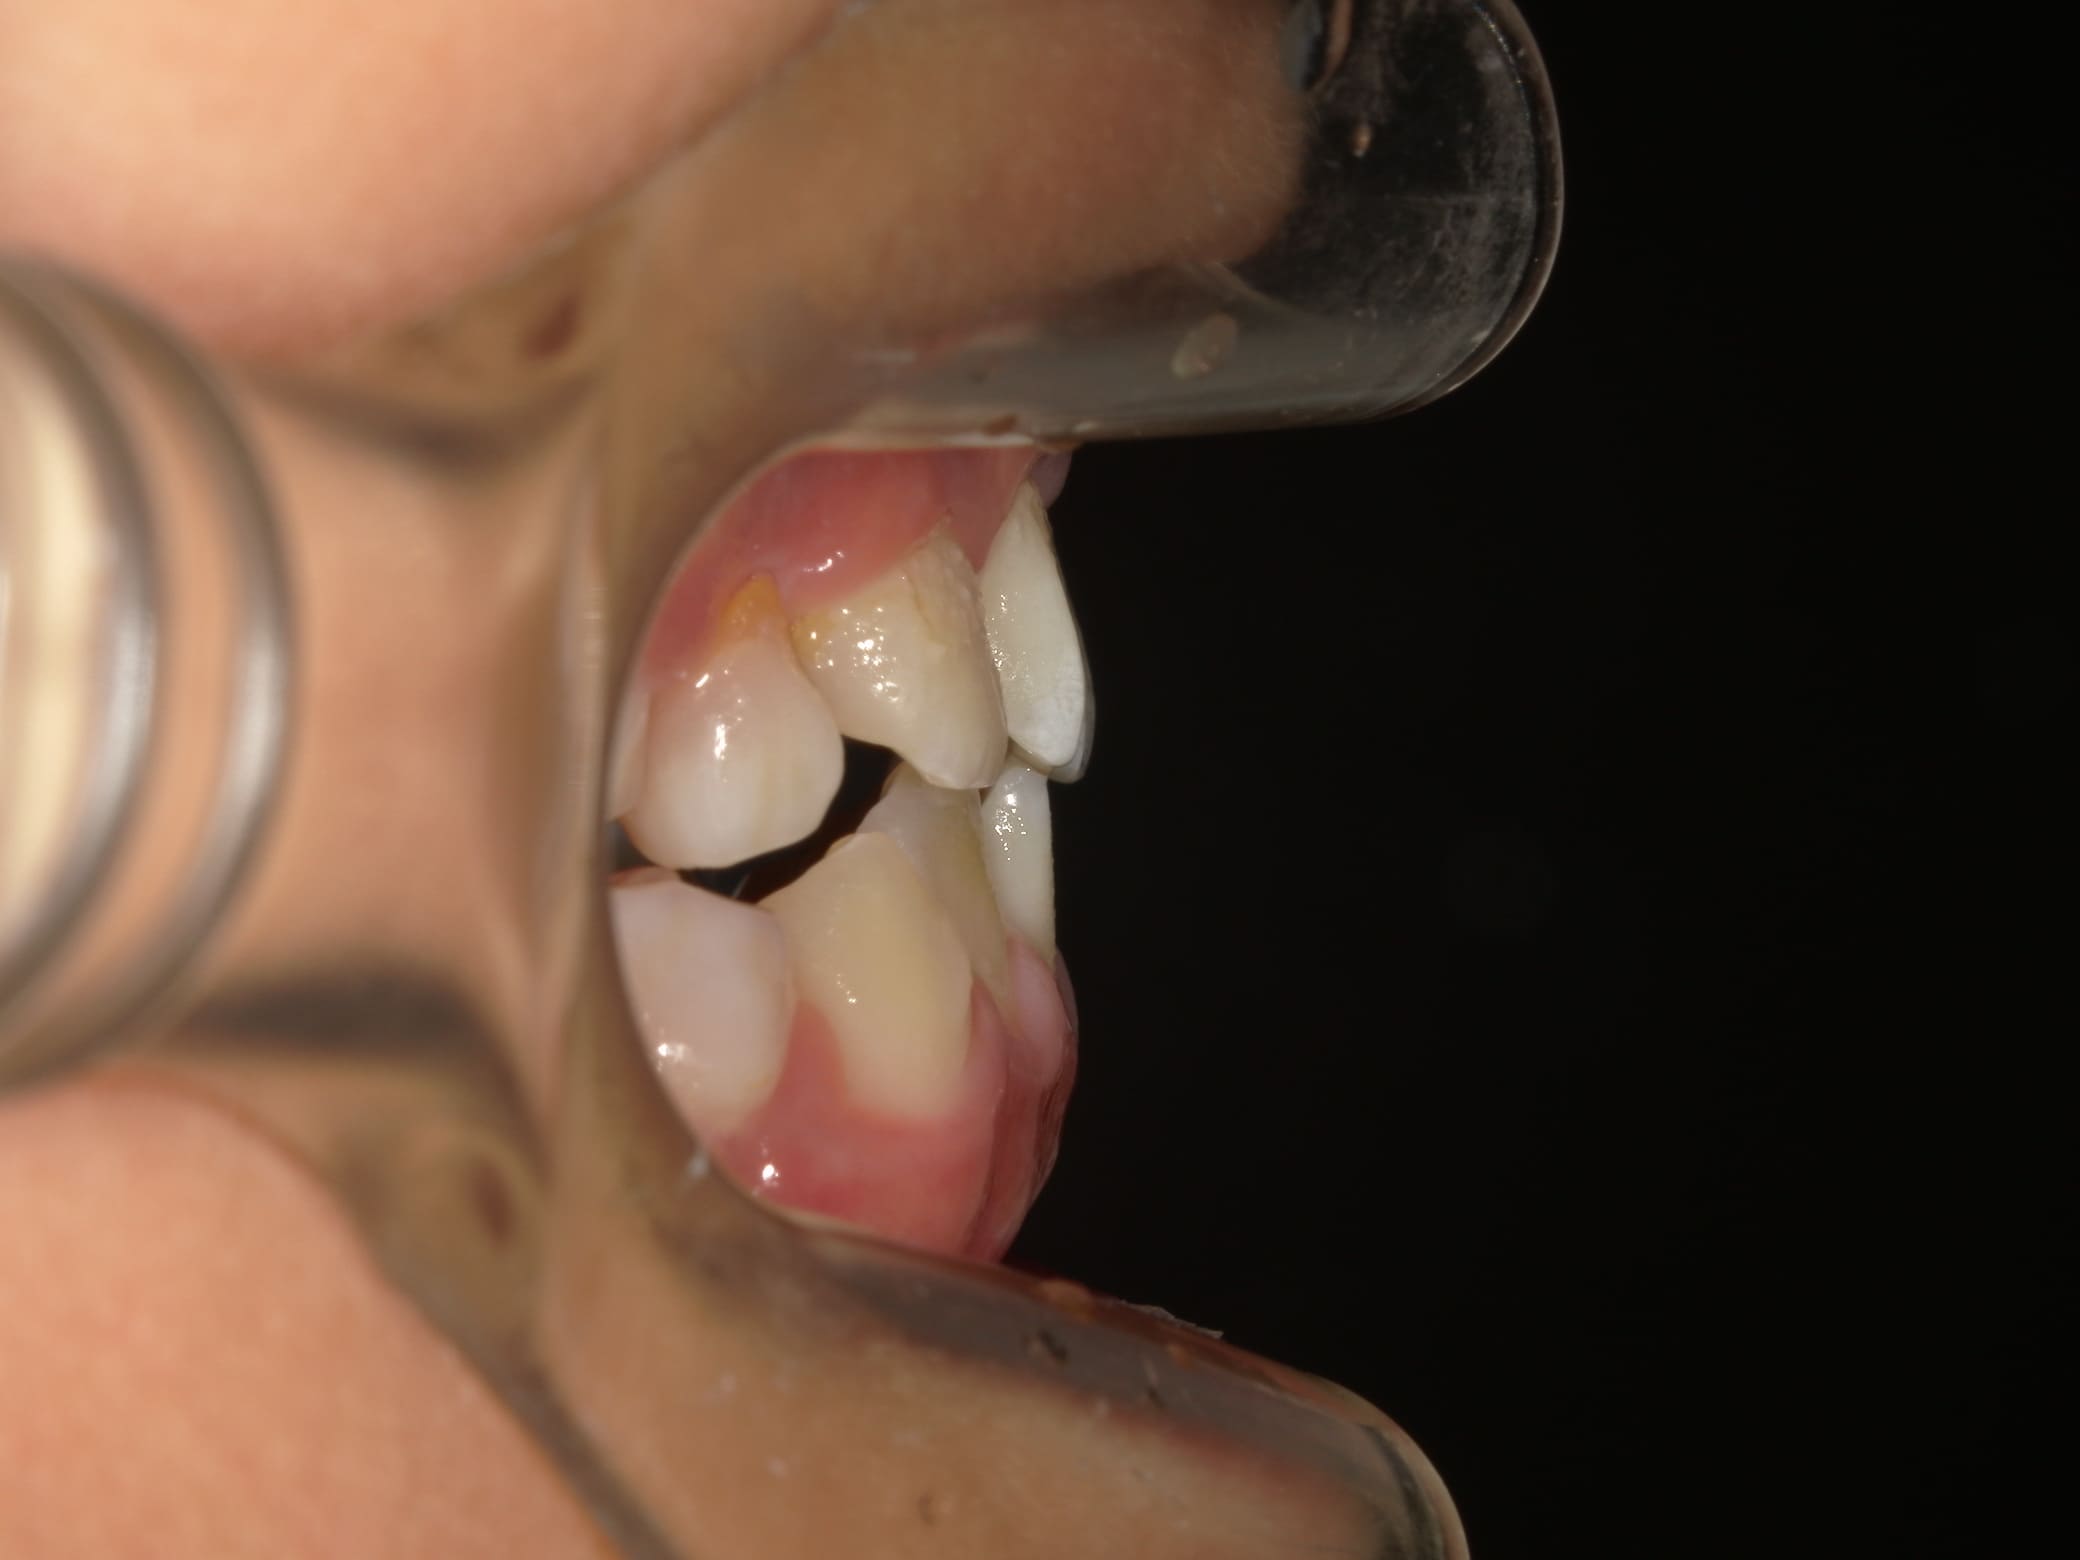

| 年齢・性別 | 8歳11ヶ月の男児 |

|---|---|

| 主訴 | 上顎の永久歯の位置がおかしいとのことで来院。萌出していない右上の前歯の状態に不安を抱えられていました。 |

| 治療期間・回数 | 約3年2ヶ月 |

| 費用 | 440,000円(税別) |